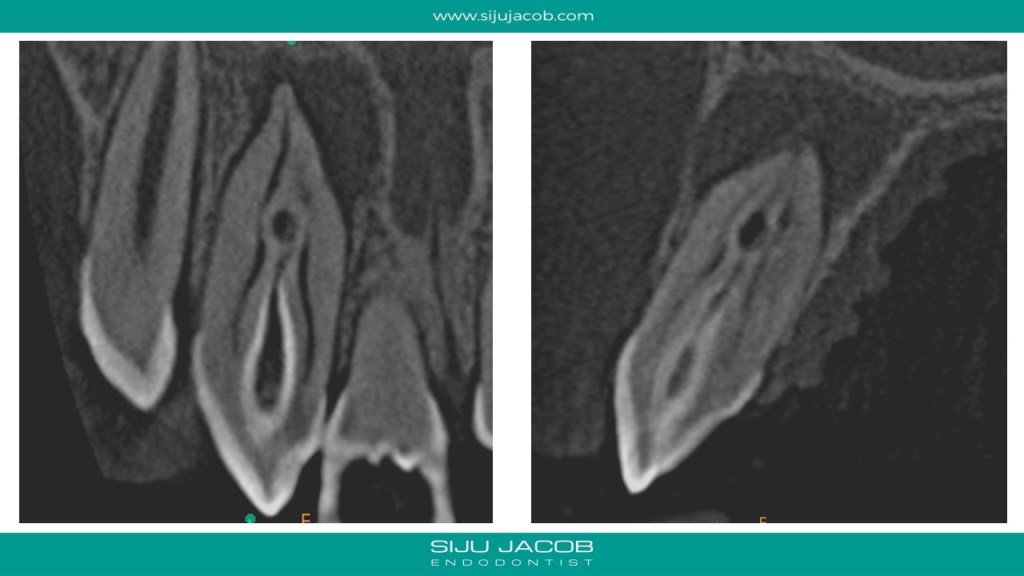

I initially thought of treating only the necrotic dens in this case because the tooth responded to heat and cold indicating that the apical lesion was probably from the dens. But, after the initial visits, the patient had persistent pain. So, I opened up both the canals, one of which was very hyperemic. I put this tooth on calcium hydroxide for 12 months and Obturated after the lesion healed. Placed Fiber-posts to strengthen the tooth. No crown for now.